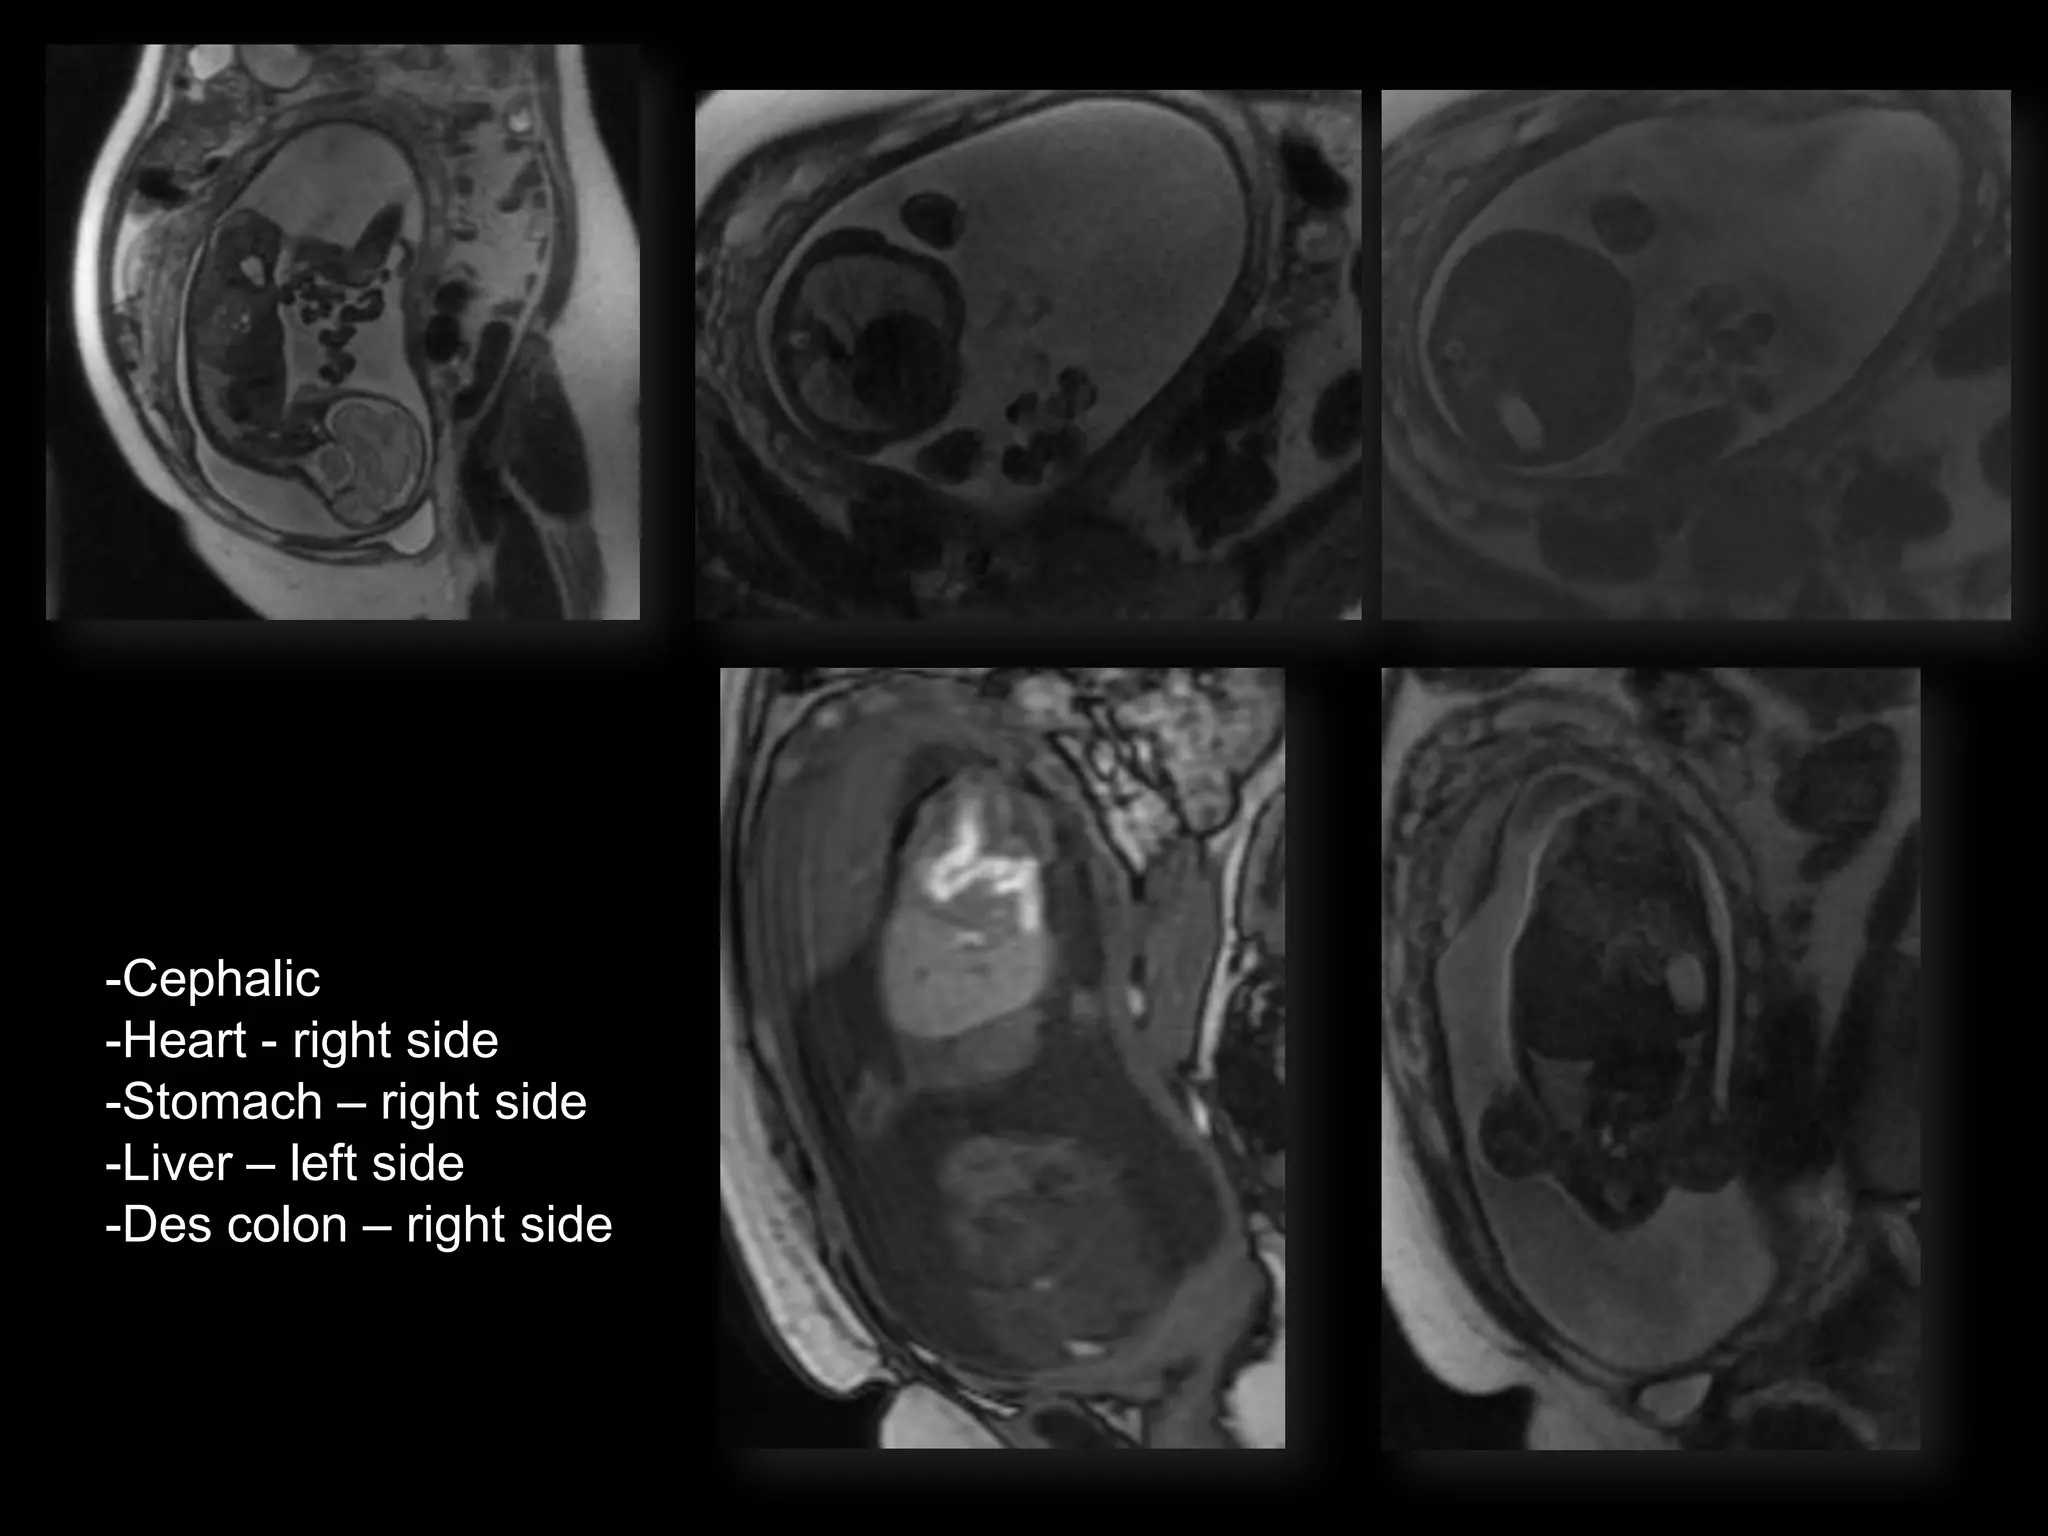

LUS โ€“ Cephalic

POSTNATAL BABYGRAM

-Cephalic

-Heart - right side

-Stomach โ€“ right side

-Liver โ€“ left side

-Des colon โ€“ right side

Situs Inversus Totalis

-Cephalic -Heart - rightside -Stomach โ€“ right side -Liver โ€“ left side -Des colon โ€“ right side

Situs Inversus Totalis โ€ข3-5% with cardiac abnormalities โ€ข 25% with primary ciliary dyskinesia (PCD) โ€“ Kartagenerโ€Ÿs Syndrome โ€“ Chronic sinus infections; respiratory infections; infertility